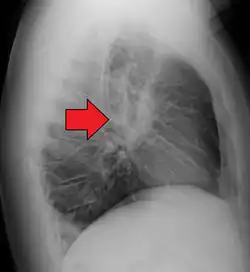

CT scan of the chest showing lymphadenopathy (arrows) in the mediastinum due to sarcoidosis

Diagnosis of sarcoidosis is a matter of exclusion, as there is no specific test for the condition other than the Kveim-Siltzbach test. To exclude sarcoidosis in a case presenting with pulmonary symptoms might involve a chest radiograph, CT scan of chest, PET scan, CT-guided biopsy, mediastinoscopy, open lung biopsy, bronchoscopy with biopsy, endobronchial ultrasound, and endoscopic ultrasound with fine-needle aspiration of mediastinal lymph nodes (EBUS FNA). Tissue from biopsy of lymph nodes is subjected to both flow cytometry to rule out cancer and special stains (acid fast bacilli stain and Gömöri methenamine silver stain) to rule out microorganisms and fungi.[99][100][12][101]